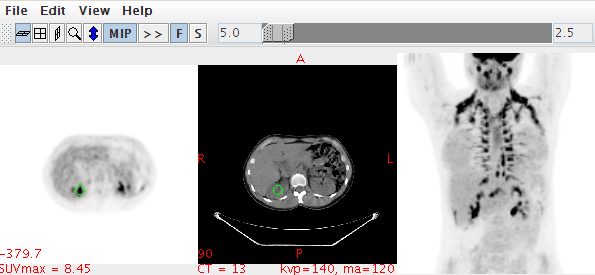

その後、ビューワが起動し、PET画像のMIP画像が回転し始めます。

(表示)

このとき、すでに2つのシリーズはフュージョンされており、拡大、縮小、ウィンド二ング、ページングを同期して、簡単に観察することができます。動画表示を停止するときは、MIPボタンを押すと停止します。再度見るときは、もう一度MIPマークを押して、MIPマーク隣の>>マークでスタートストップを調整します。

その他、FボタンとSボタンはそれぞれ正面と側面のリセット表示になっています。マウスカーソルを画像上に持っていけば、SUVbw(Max)(以下、SUVと略す)とHU値が表示されます。もし、DICOMタグに綺麗に放射線医薬品情報シーケンスが付随していない場合は、MaxCountが表示されます。

(PET画像上にSUVbwmaxが表示されている)